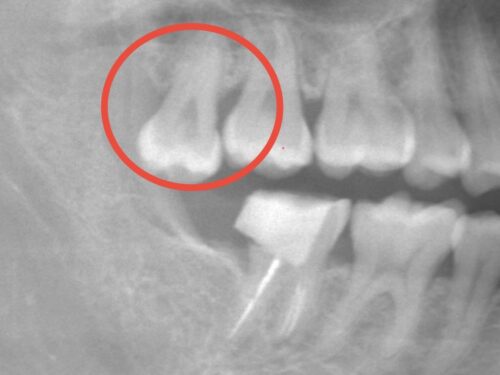

レントゲン検査を行い、破折の程度と周囲の骨の状態を確認しました。また、移植に使用できる親知らずについて評価しました。

赤い円で囲まれた部分に上顎の親知らずが存在していることが確認できます。

今回のケースでは、使用していない上顎の親知らずがあり、形状も移植に適していたため、自家歯牙移植が最適な選択肢と判断しました。

レントゲン写真で示されている上顎の親知らずを抜歯し、移植しました。